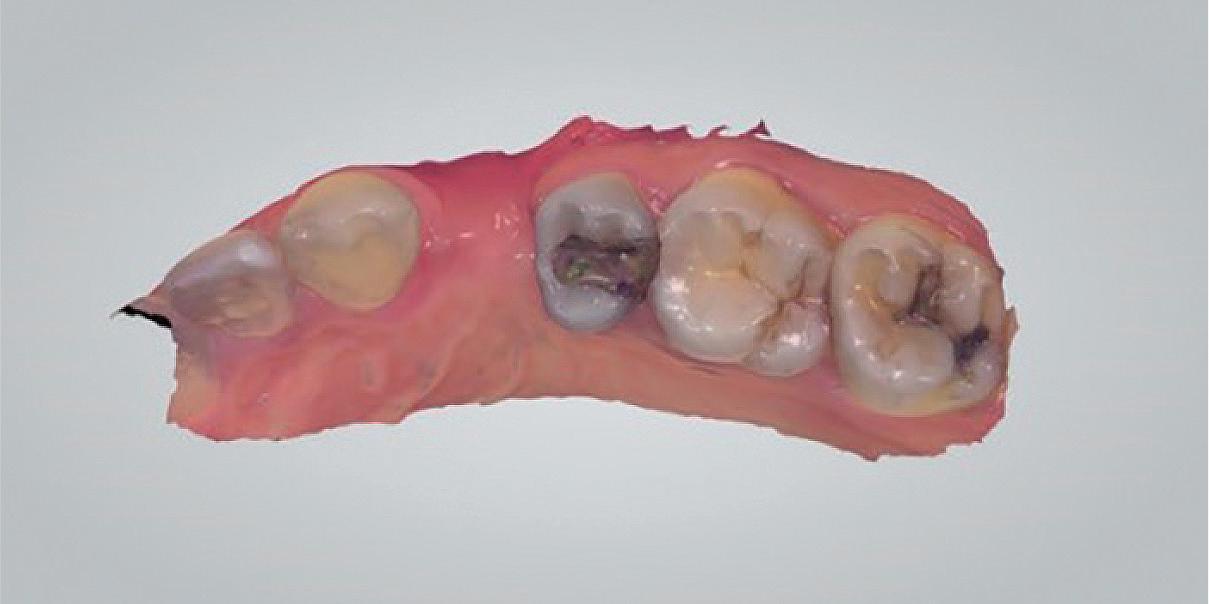

Clear radiographs are essential to accurate diagnosis and are a special test that dentists per form regularly many times throughout the day. Following the ALARA principle, we want to ensure we take a minimal number of radio graphs to ensure low radiation dosage so to repeat radiographs due to operator error should be avoided. The use of film holders allow the clinician to visualise how the radiographs should be taken to optimise the clarity of the image and ensure the diagnostic value of the image. Hawe Solutions x-ray film holders...

• Allow exact posi tioning of the film or phosphor plate relative to the tooth - no bending and thus no distortion;

• Require no guesswork - exclusive, automatic reliance on the extraoral aiming and centring device;

• Deliver semi-reproducible images (quasi standardisation)the use of film holders allows some sense of reproducibility for assessment over time; and

• Produce optimally clear radiographs.